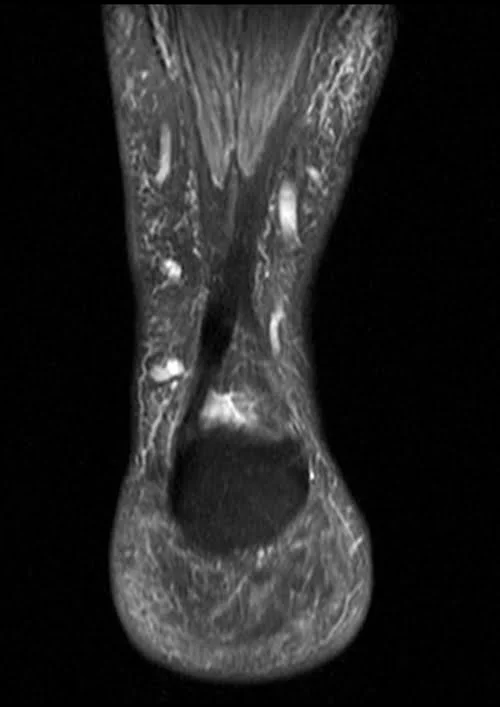

MRI ANKLE COR PD FS IMAGE 1 - MRI